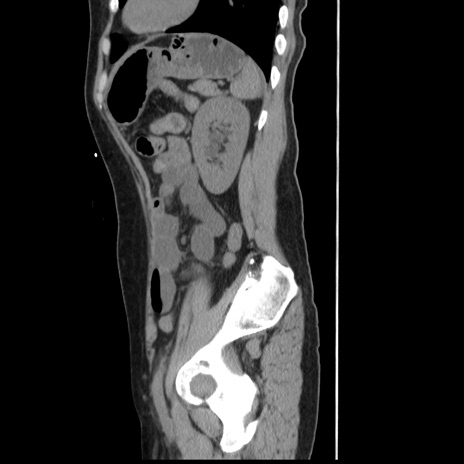

冠状断像

【症例】 50歳代女性

【主訴】 腹痛

【現病歴】前日生レバーを食べた。今朝に排便あり。 昼前に突然発症の腹痛を生じ、当院救急外来を受診した。

【既往歴】 子宮筋腫にてで子宮全摘後

【身体所見】 意識清明、腹部:平坦、軟、下腹部やや左を中心に圧痛・反跳痛あり、筋性防御あり

【データ】WBC 7800、CRP 0.07